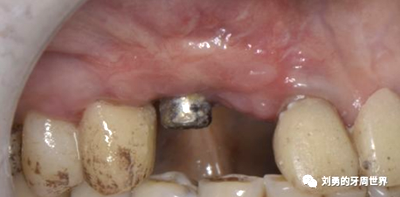

下面這個(gè)是我使用國(guó)產(chǎn)的替代品的病例:

可見右上前牙植體頰側(cè)無附著齦